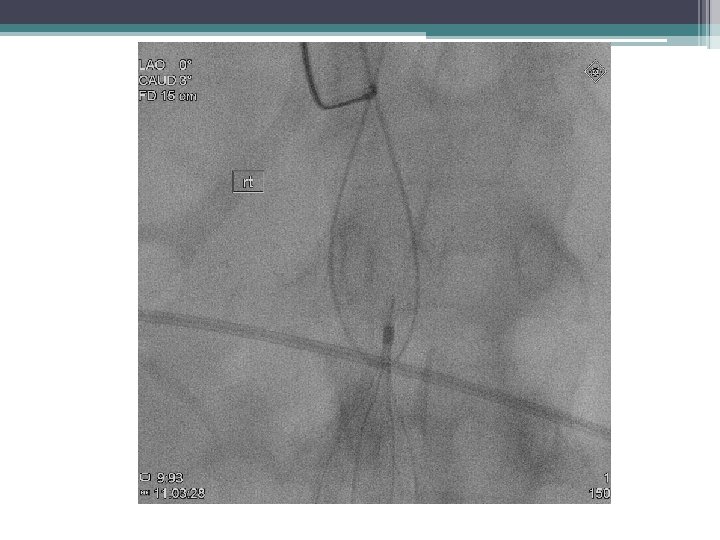

Retrieval Technique Standard • Snare • Large sheath Complex • Filter Specific • Can be adapted to retrieve permanent filters

Embedded • • Pass nitinol wire around apex snare Pass wire Balloon inflate Endobronchial forceps Excimer Laser

Migrate Tilt 11/2012 12/2012

Tilt